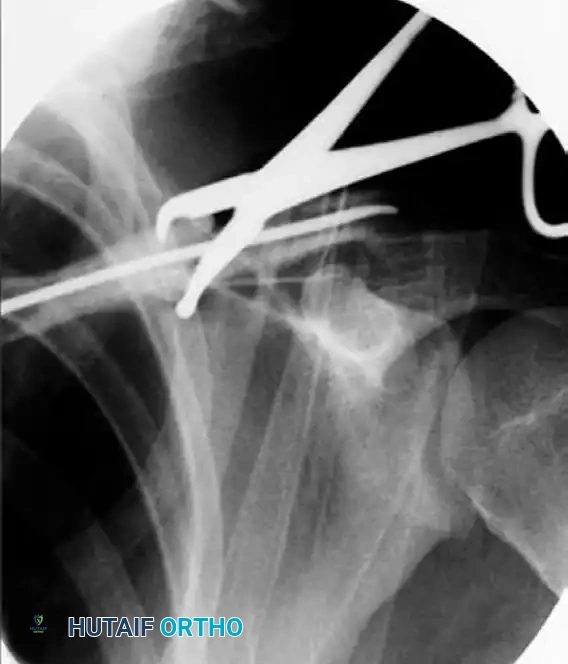

• Fluoroscopic Guidance: Utilize intraoperative fluoroscopy to determine the optimal osteotomy plane. A K-wire or a drill bit can be placed over the bone to simulate the cut and verified under C-arm imaging.

Fluoroscopic determination of osteotomy plane

FIGURE 1: Determination of the osteotomy plane using fluoroscopy. A drill bit or K-wire is used to map the trajectory before the definitive cut is made.

• Execution: Once the plane is confirmed, use a fine oscillating saw or an osteotome to carefully divide the malunion. Copious irrigation must be used during sawing to prevent thermal necrosis of the bone.